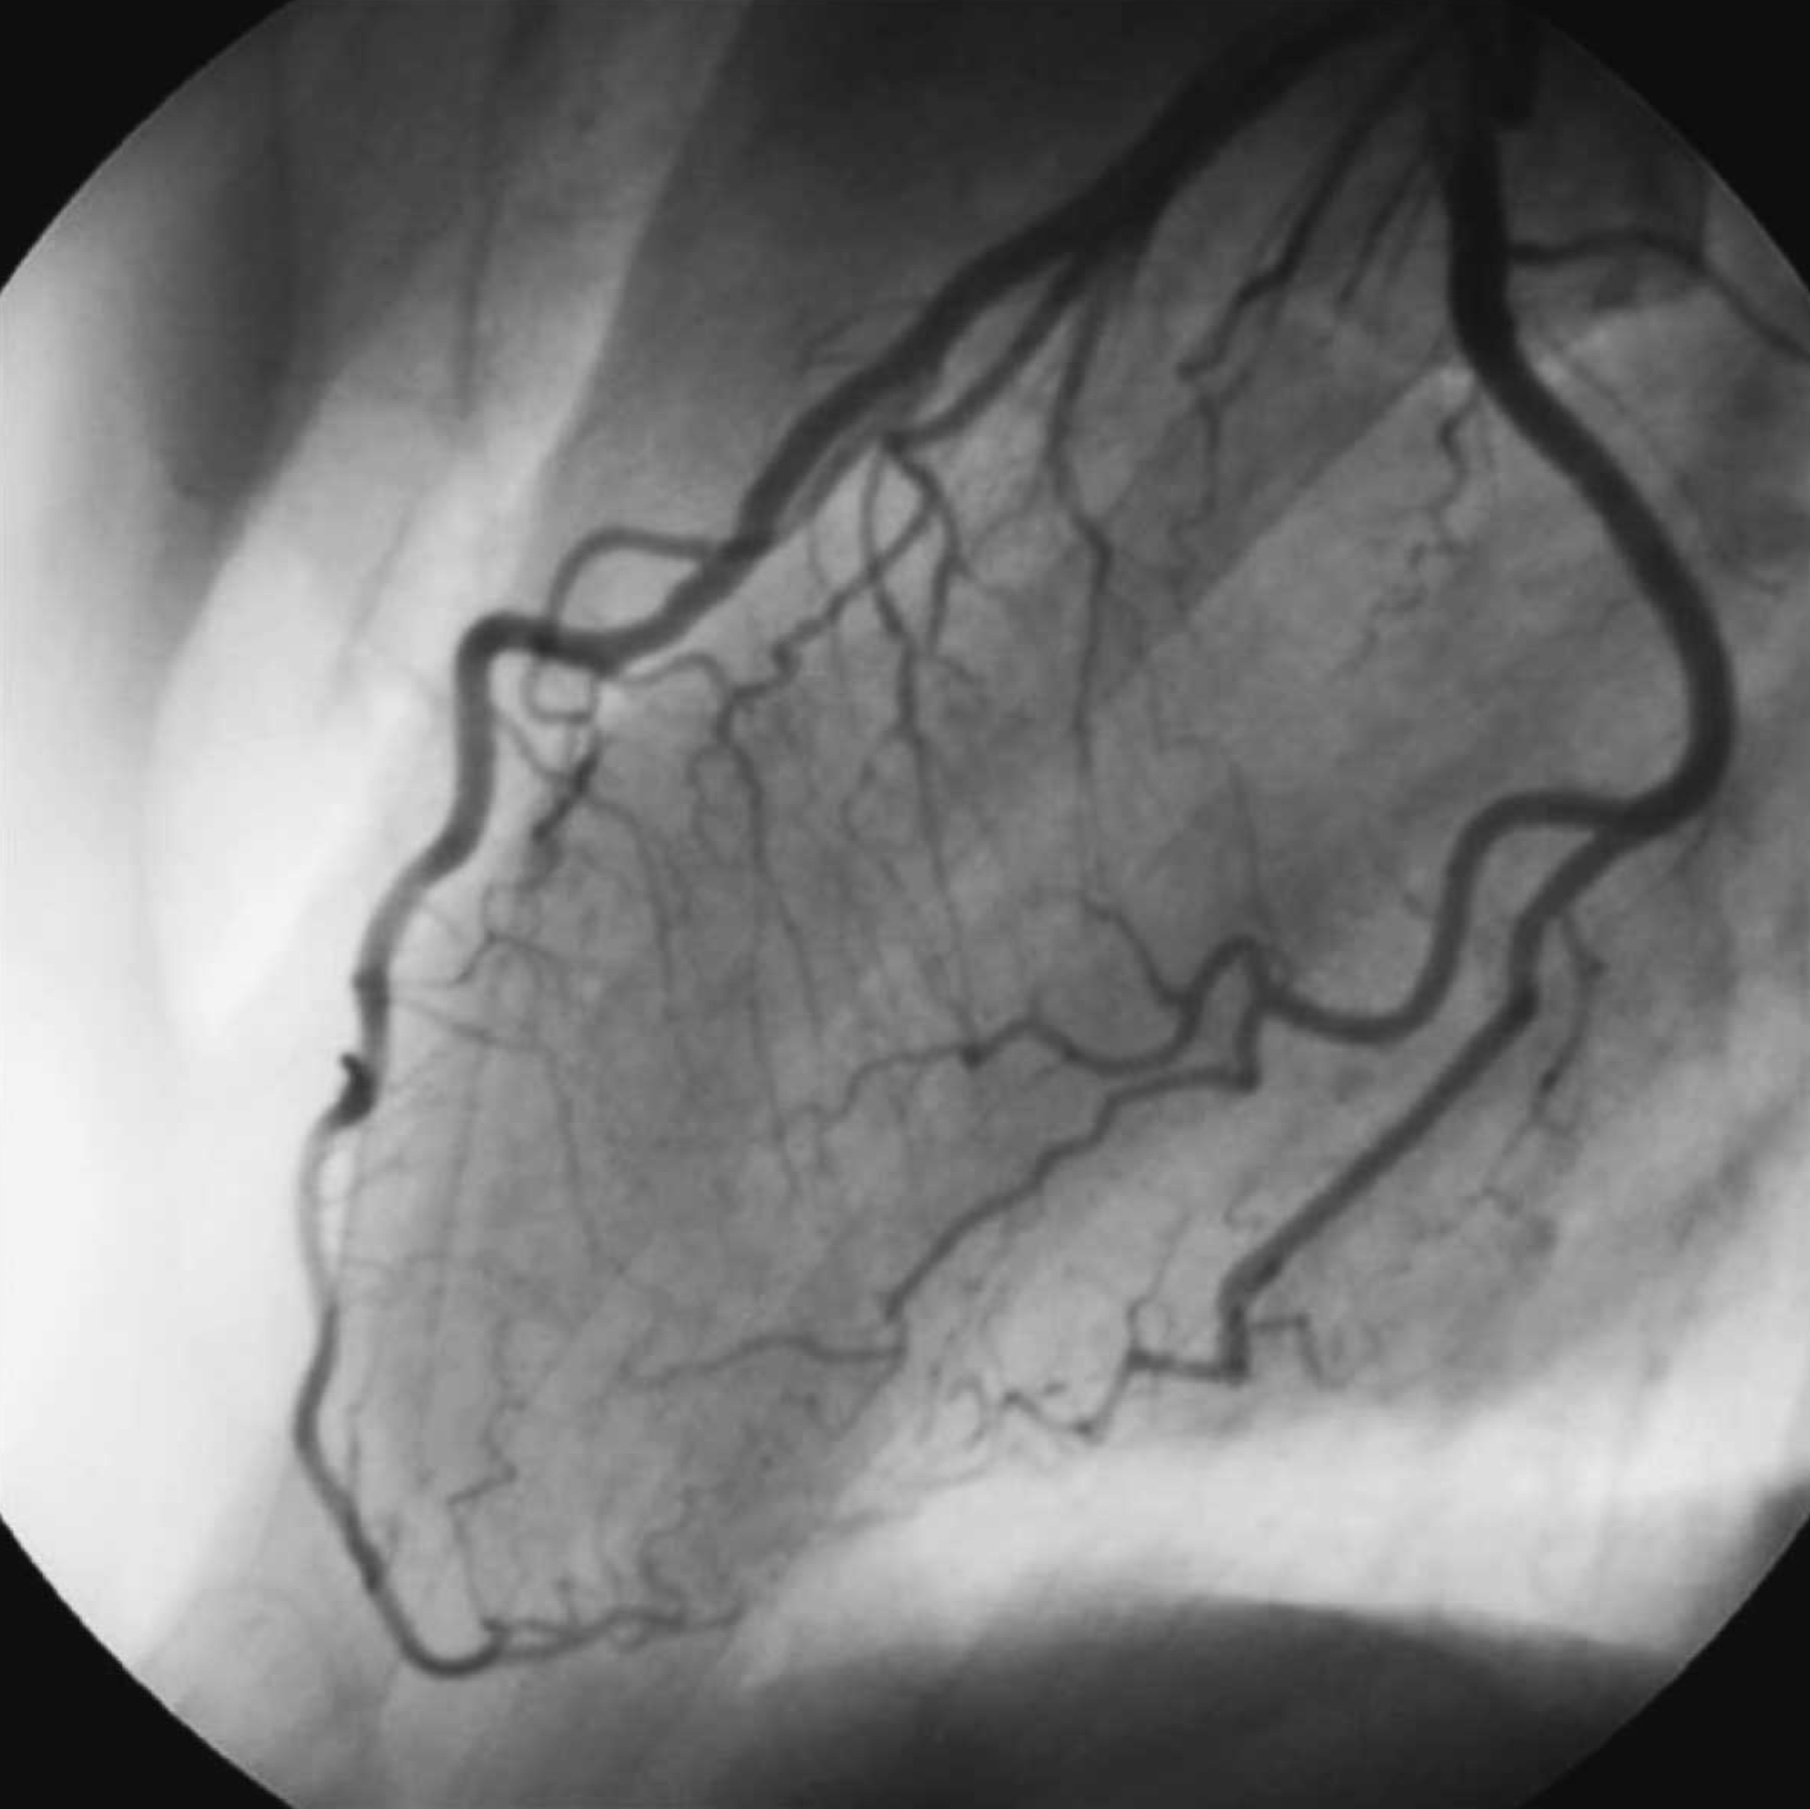

1. An 63 year old man has a heart arrhythmia. Upon further investigation, an angiogram shows an occlusion of the proximal right coronary artery. Why would this potentially cause arrhythmia? Discuss the anatomy and relationships of the right coronary artery and branches as well as the complementary venous drainage. Include mention of any commonly seen anatomical variances, if any.

2. A patient is shown to have a partial occlusion of their anterior interventricular artery (left anterior descending artery). Discuss the anatomy and relationships of the left coronary artery and branches as well as the complementary venous drainage. Why is an occlusion in this artery especially dangerous and what potential surgical solutions can be used as treatment? Include mention of commonly seen anatomical variances, if any.